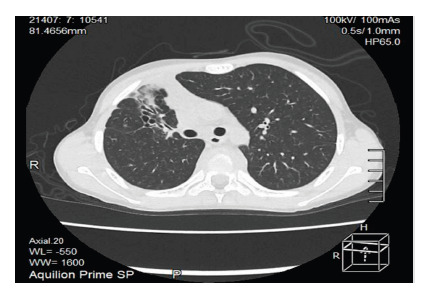

Primary adrenal insufficiency is the result of impaired steroid synthesis, adrenal destruction or abnormal development of the adrenal gland affecting the adrenal cortex. Tuberculosis is one of the main causes in developing countries. We present the case of a 10-year-old male patient diagnosed with adrenal insufficiency two years earlier with regular treatment, who was admitted for adrenal crisis. A thoraco-abdominal tomography was carried out during hospitalization, which showed cylindrical and traction bronchiectasis associated with cicatricial atelectasis in the right upper pulmonary lobe, enlarged adrenal glands with foci of calcification, as well as a dense posterior perivertebral mediastinal collection also involving vertebral bodies with lytic resorptive foci, findings consistent with systemic tuberculosis. Treatment for tuberculosis started based on this diagnosis. During course of the disease, the first phase was completed with four drugs, and the second phase included isoniazid and rifampicin with favorable clinical response.